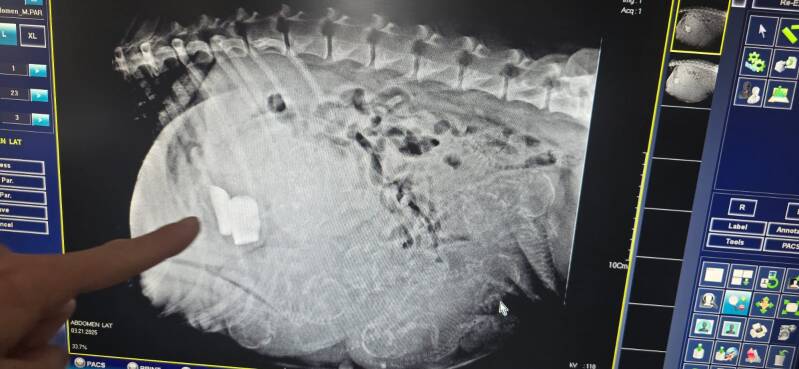

Heute am 17.02. zum Ultraschall

Die Verpaarung Atina und Pino war erfolgreich, wir erwarten um den 23.03. die kleinen Bärchen 🥰😍